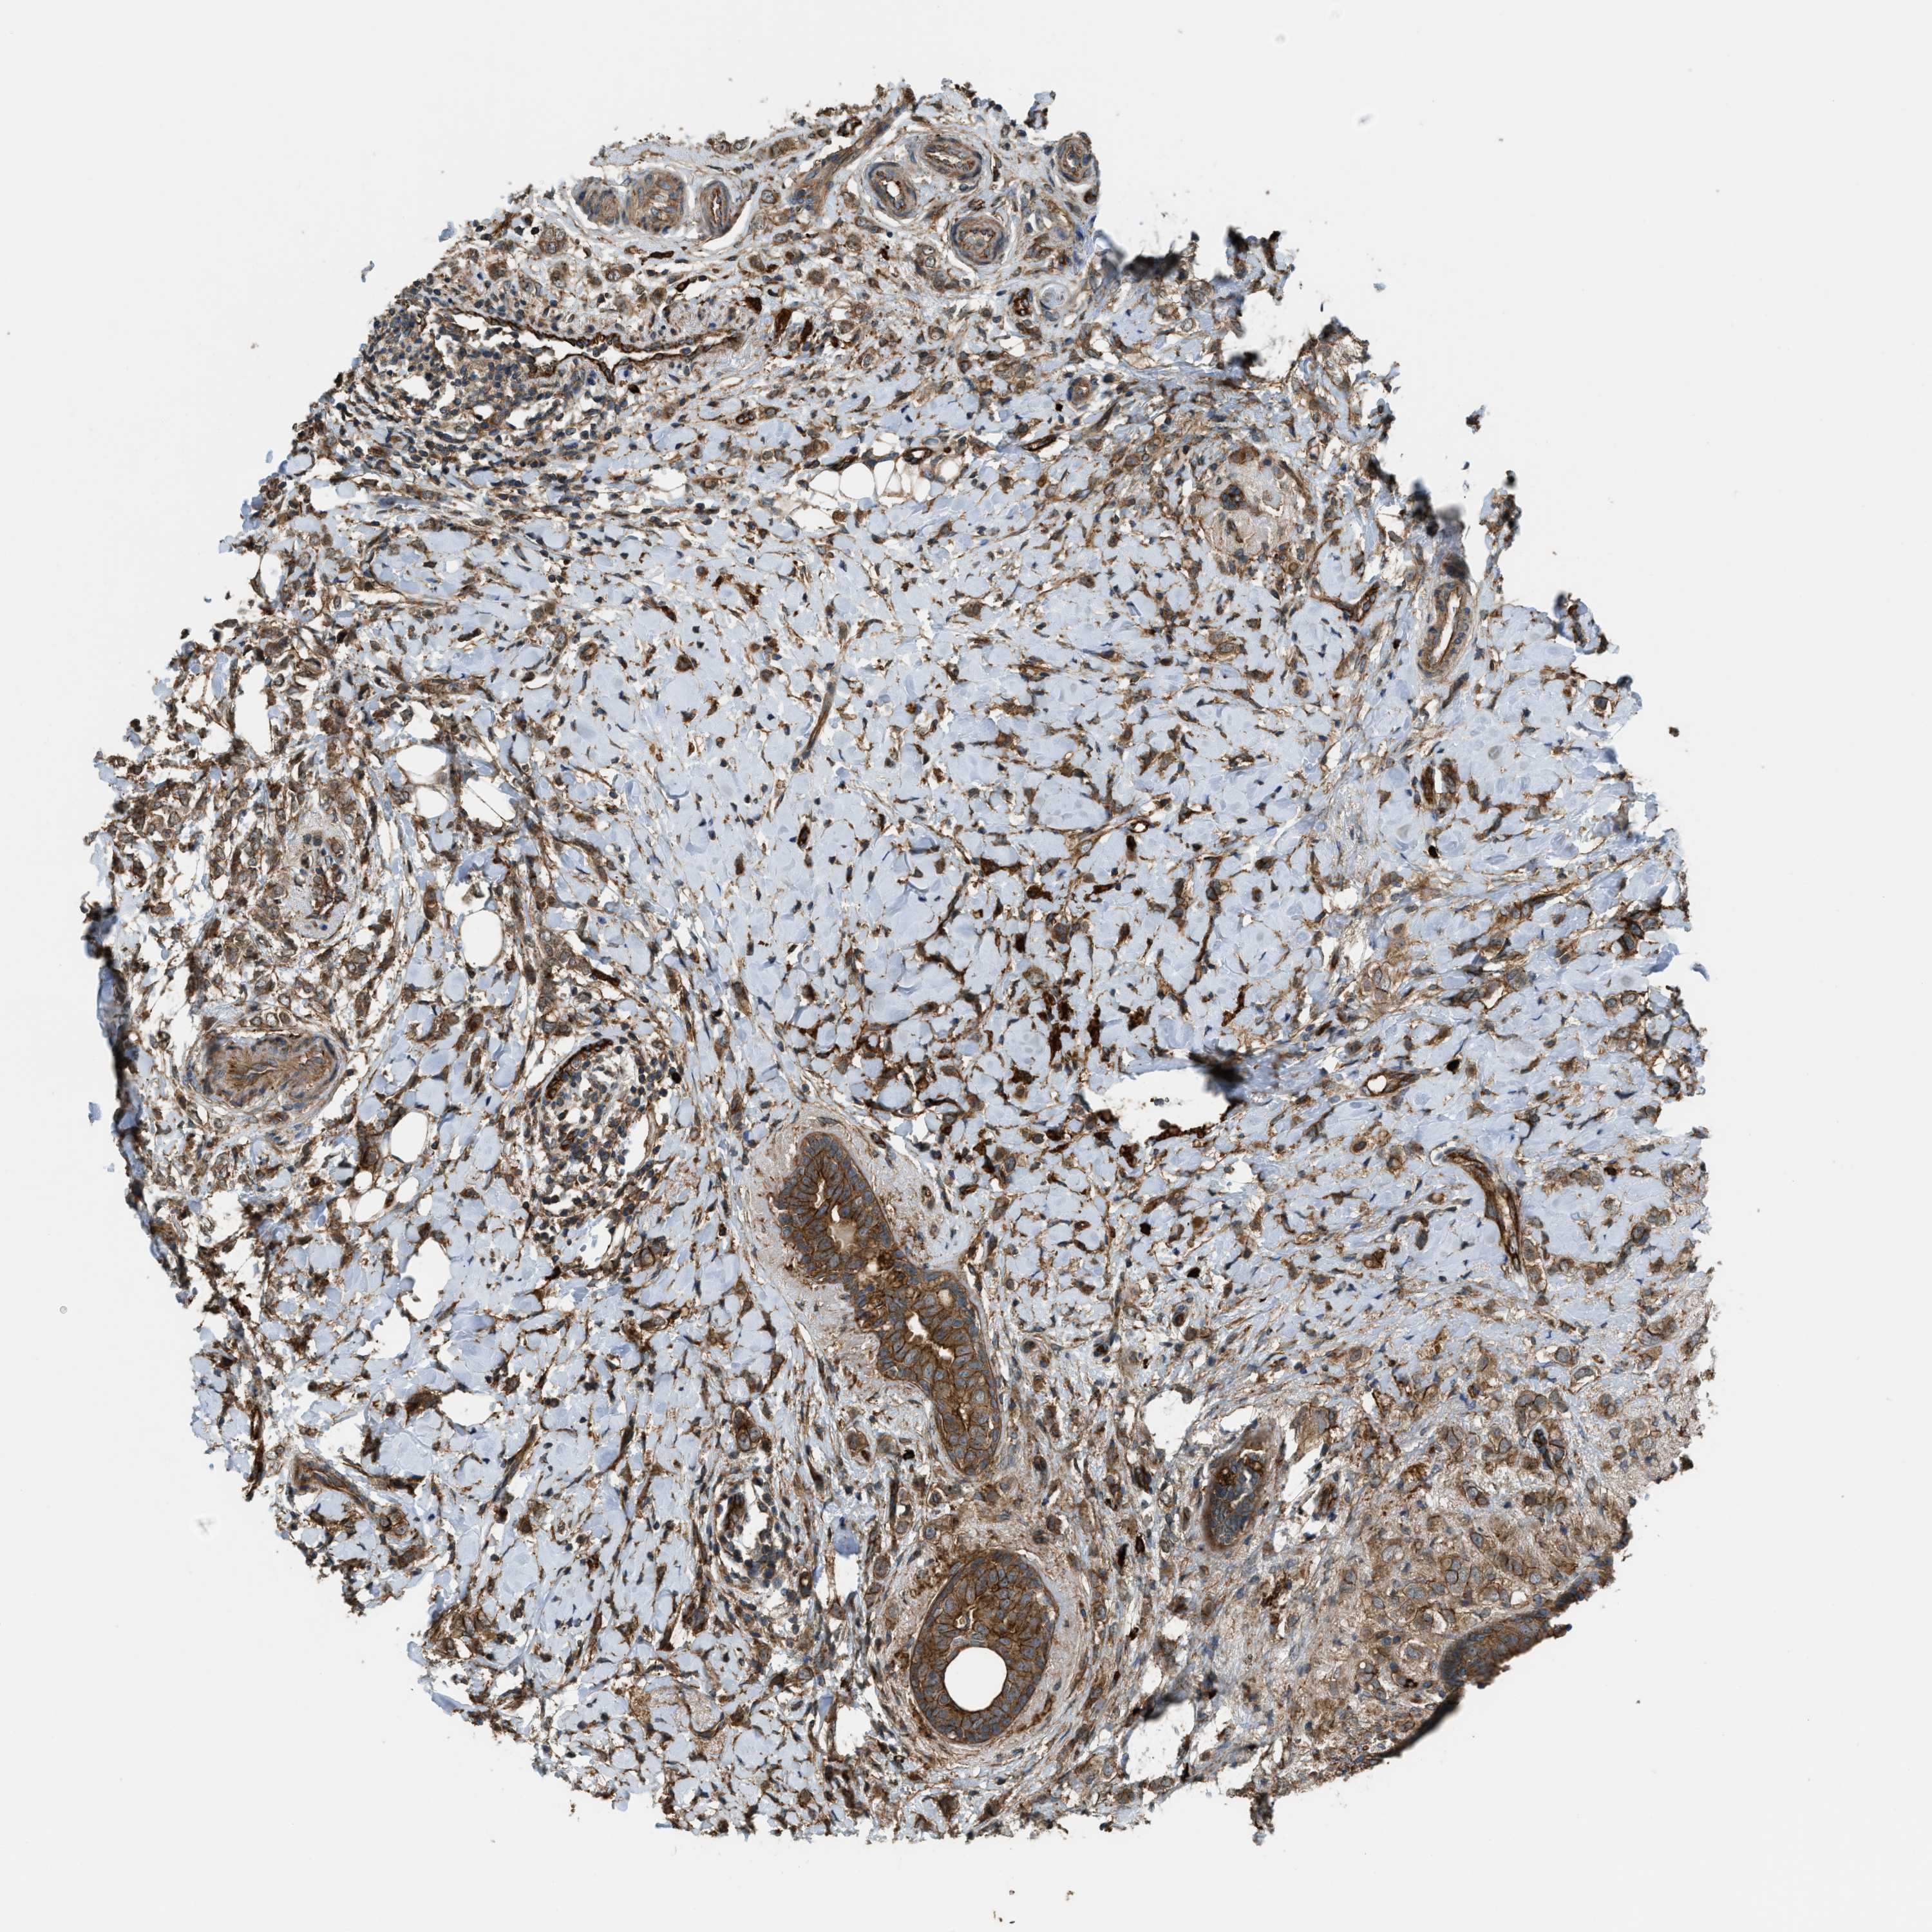

CANCER BREAST CANCER Show tissue menu

BRCA TCGA BRCA VALIDATION PROTEIN EXPRESSION